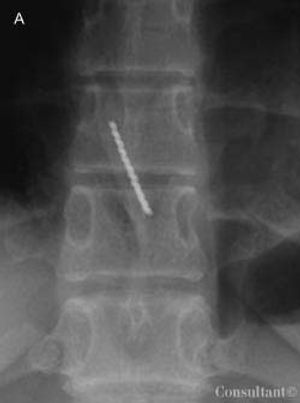

A 16-year-old girl of normal weight for height (body mass index, 21) was evaluated for a 6-month history of binge-purge cycles and amenorrhea. She met the diagnostic criteria for bulimia nervosa and began treatment that involved a multidisciplinary team. During the second month of therapy, the patient presented to the emergency department after she accidentally swallowed a toothbrush while trying to induce vomiting with the brush’s handle.